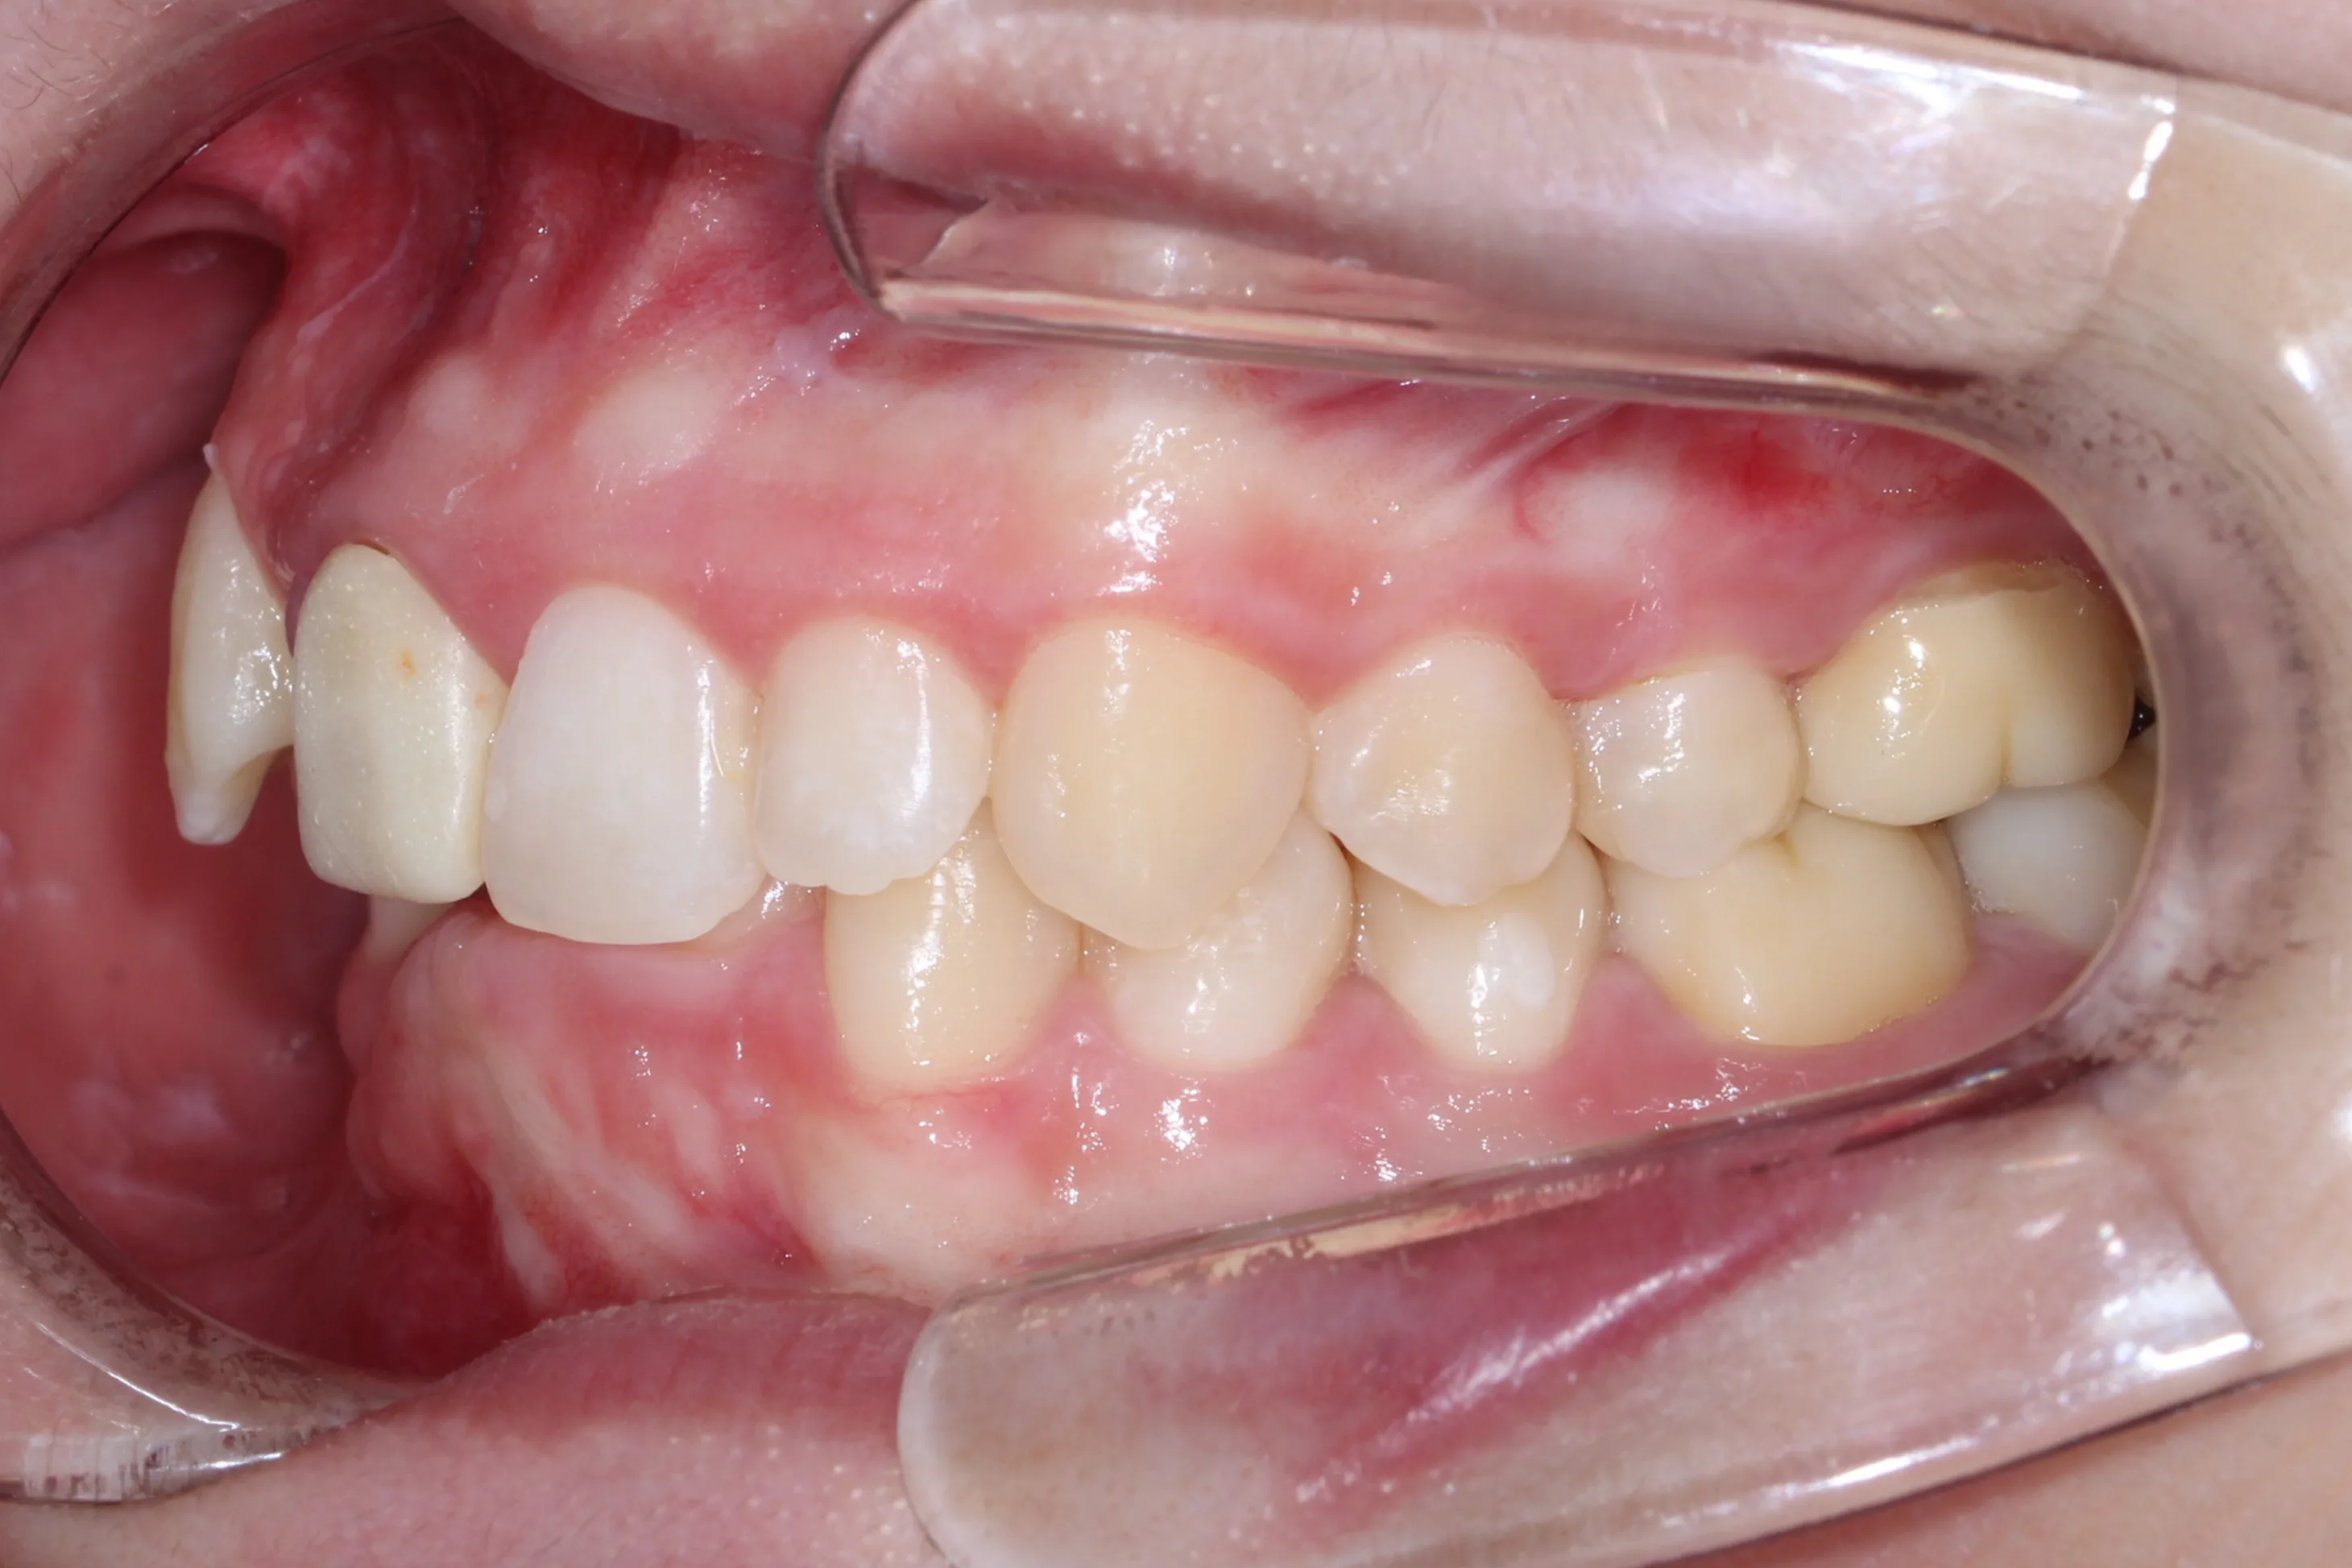

만 21세 환자로, 기존에 사고로 여러 치아를 다치고 상실한 상태로 매우 심한 교합무너짐이 있었습니다.

치료전 (Before)